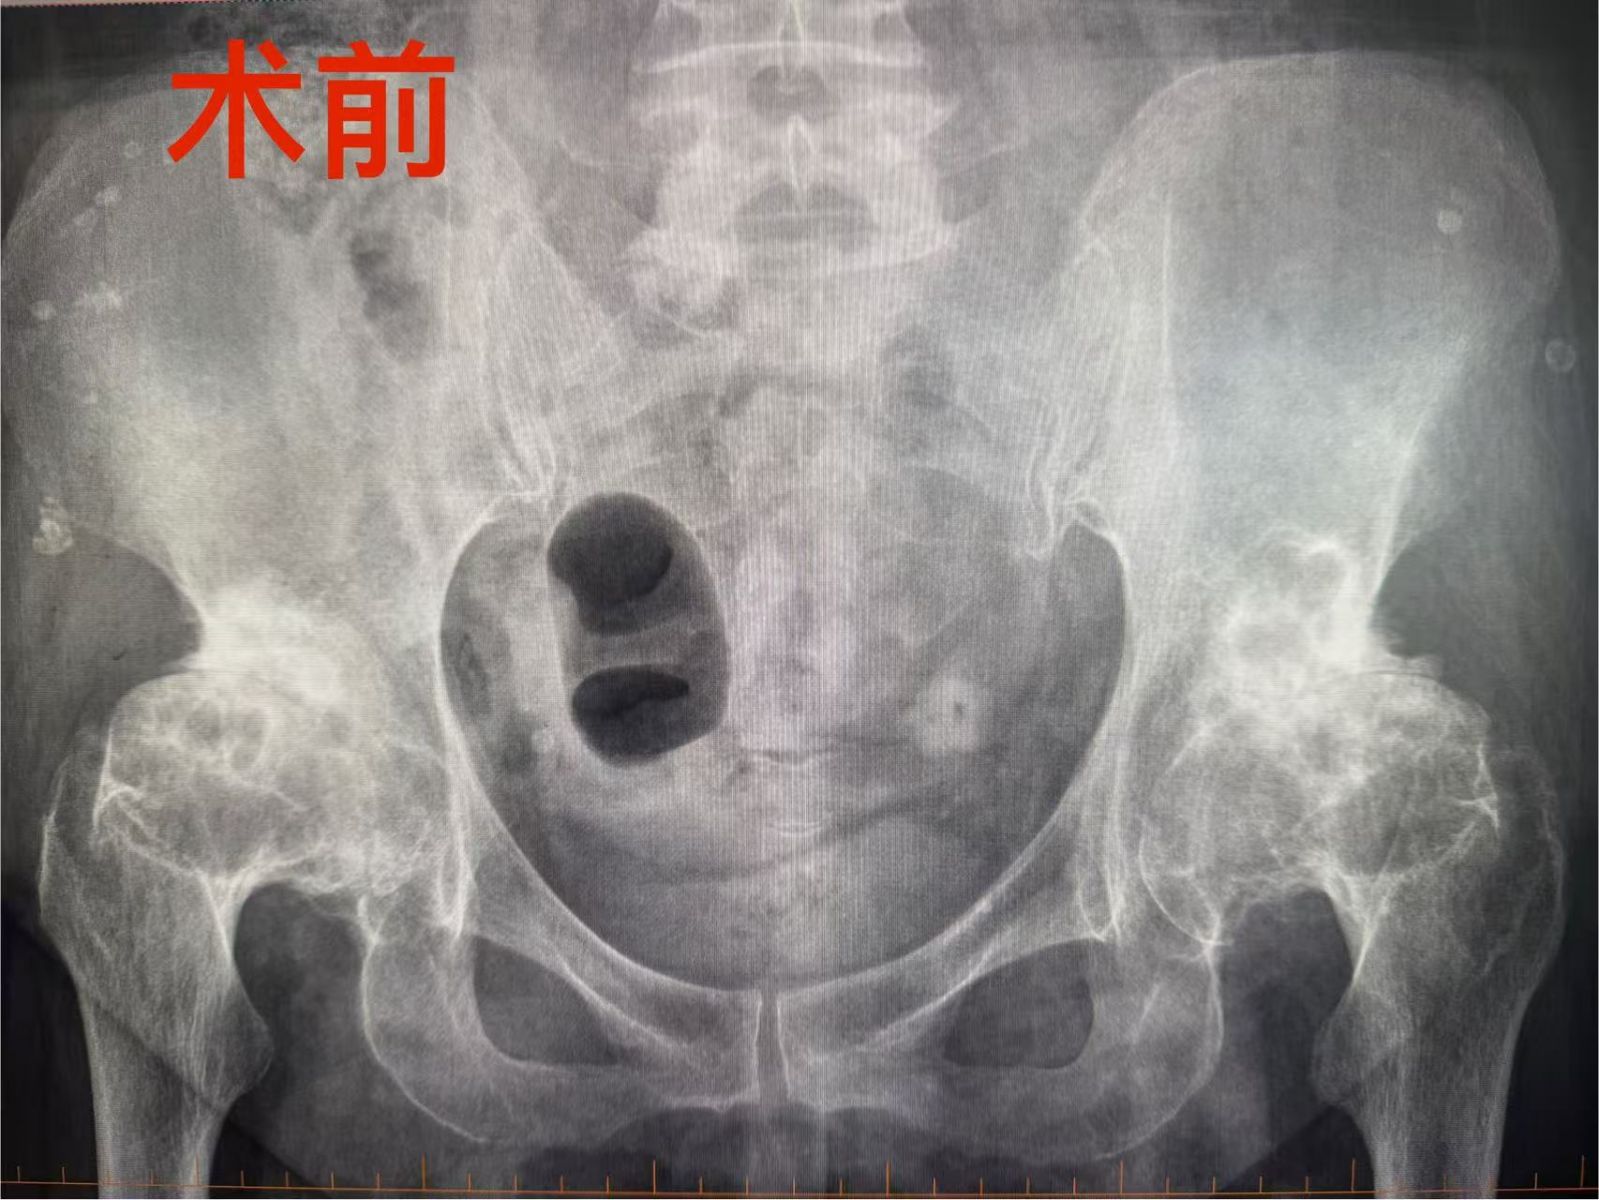

今年年初,老人的髋关节疼痛越发加剧,行走变得更加费力,于是告诉了外地子女,子女陪同老人来新城医院就诊检查,骨盆DR片提示:双侧髋关节退行性变,考虑双侧股骨头缺血性坏死。家属决定办理住院,为老人进行手术治疗。

骨科王凯医生接诊,耐心细致询问病情、查体,完善各项血液检查,骨科蒋刚主任邀请相关科系专家,全面评估老人健康状况。面对老人和家属对“双侧股骨头缺血性坏死”诊断的疑问,蒋主任详细解答,解除家属的疑惑,并为老人制定了细致的手术治疗方案:治疗双侧股骨头缺血性坏死,需分步手术治疗,建议先做右侧,半年后再做左侧。老人和家属非常认同及认可。蒋刚主任凭借丰富的临床经验和精湛的医术为老人实施右侧全髋关节置换手术,术后在医务人员的精心治疗护理下,老人很快康复出院。